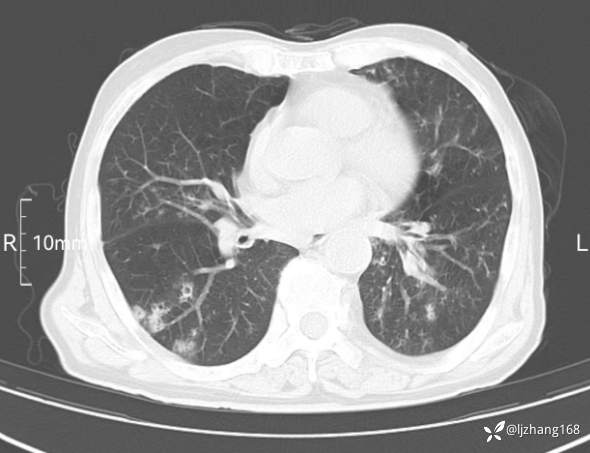

辅助检查:胸部CT:双肺肺气肿,间质性病变,血气分析:PH 7.413, PCO2 29.2mmHg, PO2,81.8mmHg,乳酸 3.3mmol/1,剩余碱-4.0mmol/1,HC03 18.8mmol/1。全血超敏C反应蛋白:超敏C反应蛋白 135.60 mg/L、 白细胞 14x19^9/L,中性粒细胞11.6x10^9/L。